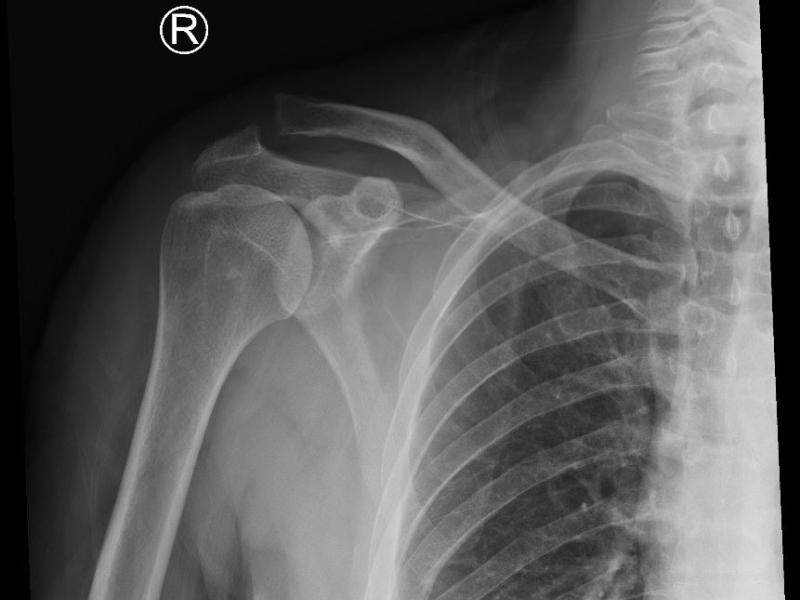

A 51 yo male presents with right shoulder pain. He tripped